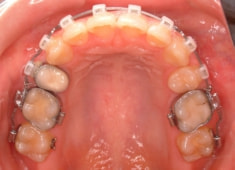

治療前